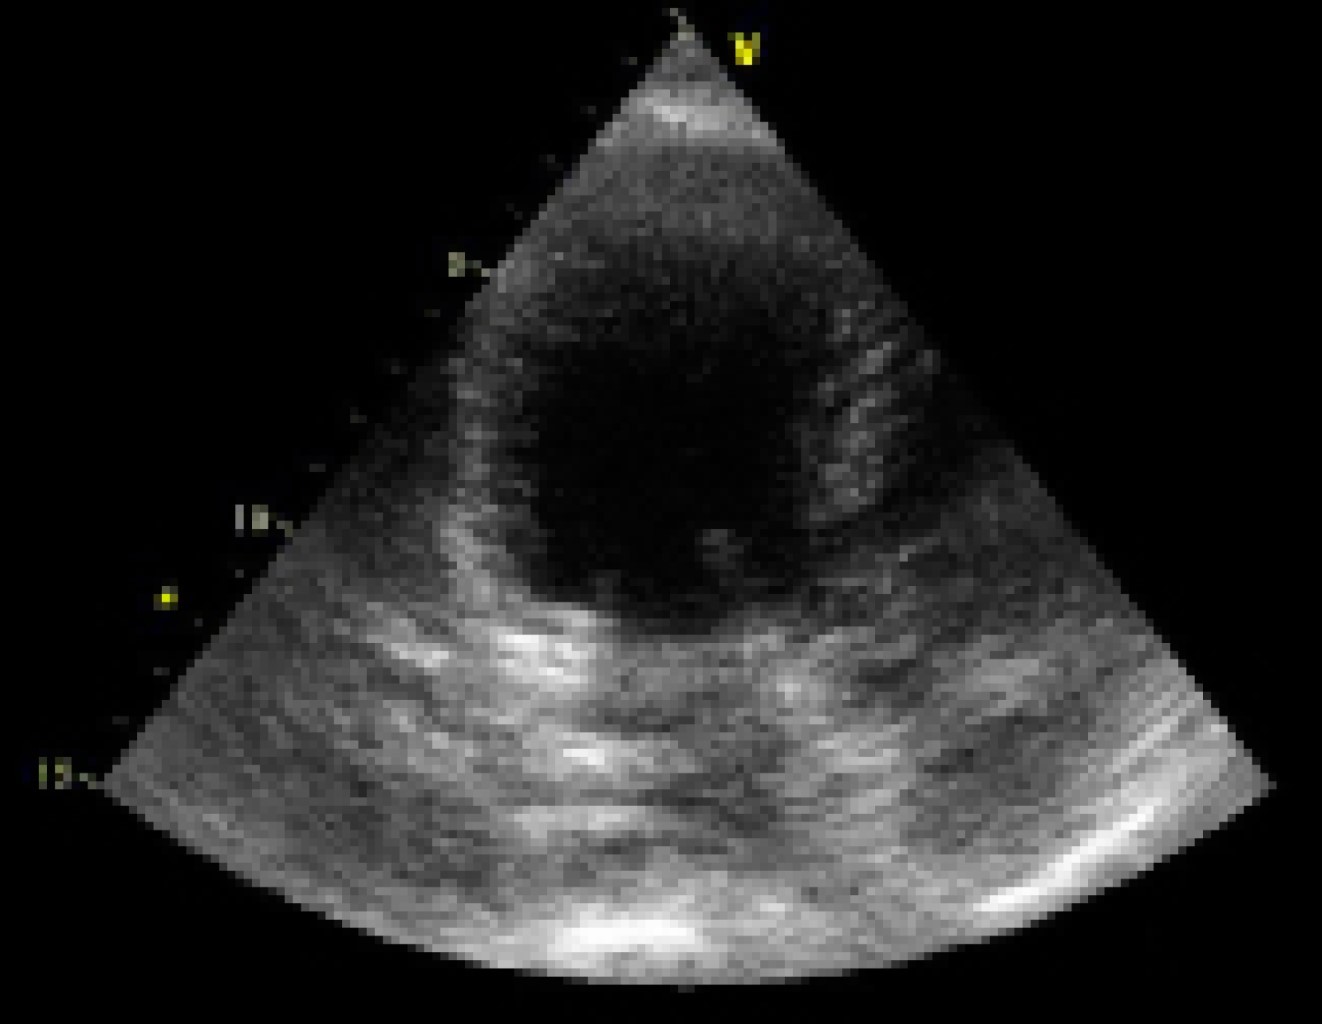

Figura 2